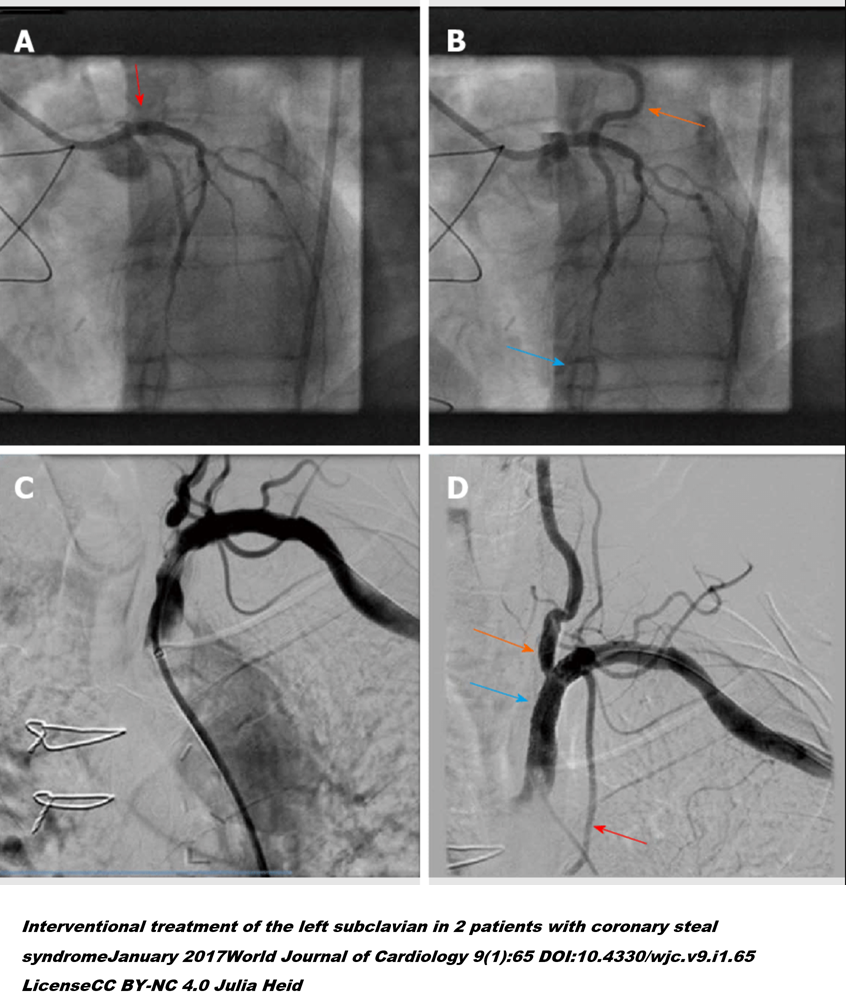

3. 관상동맥 CT 혈관조영술(Coronary Computed Tomography Angiography, CCTA)은 조영제를 사용하여 관상동맥의 혈관 상태를 시각화해 주는 검사입니다. 이 검사를 통해 우리는 관상동맥의 협착 정도뿐 아니라, 나아가서는 경화반의 성상(취약도)까지 짐작할 수 있습니다. 연구를 통해 CCTA 검사는 환자에게 추가적인 관상동맥 조영술 검사가 필요할지를 알려주고, 치료 전략을 수립하는 데 큰 도움이 된다는 것이 증명되었습니다.

CCTA.png